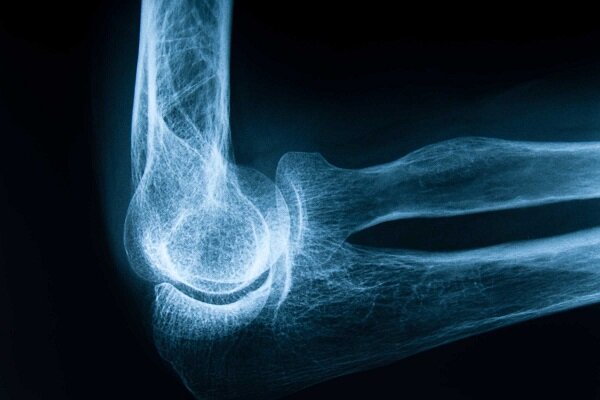

فرح اسماعیلی در گفتوگو با خبرنگار ایمنا درباره اهمیت پیشگیری از پوکی استخوان و راهکارهای ساده و مؤثر برای حفظ سلامت استخوانها اظهار کرد: بیماری پوکی استخوان در سکوت پیش میرود و تا زمانی که شکستگی اتفاق نیفتد، ممکن است فرد متوجه آن نشود، اما زمانی که استخوانی با یک ضربه ساده یا حتی عطسه میشکند، افراد تازه متوجه میشوند که تراکم استخوان آنها بهشدت کاهش یافته است.

وی با اشاره به بار مالی و روانی بیماری پوکی استخوان و با تاکید بر ضرورت پیشگیری از ابتلاء به این بیماری، تشخیص و درمان بههنگام آن افزود: شکستگیهای ناشی از پوکی استخوان به ویژه در ناحیه لگن یا ستون فقرات، میتوانند منجر به جراحیهای سنگین، بستری طولانیمدت، ناتوانی حرکتی و حتی افسردگی در سالمندان شوند و باید توجه داشت که این آسیبها، تنها آسیبهای فردی نیست، بلکه هزینههای سنگینی به نظام سلامت و خانوادهها تحمیل میکند.